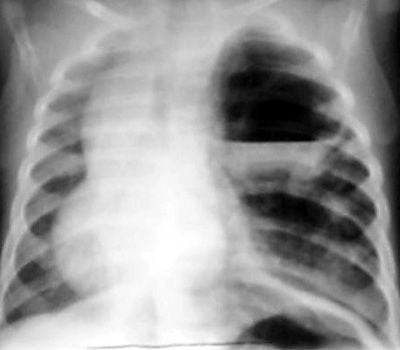

CCAM is een zeldzame aangeboren ziekte, waarbij er holtes zitten in het longweefsel van de baby. Hierdoor kunnen de longen zich soms niet goed ontwikkelen.

Een zeer kleine groep kinderen wordt geboren met een aanlegstoornis van de longen. Dit betekent dat er bij de ontwikkeling van de longen iets is misgegaan. Het meest bekend is congenitale cysteuze adenomatoide malformatie van de long (CCAM, soms ook CCAML genoemd).